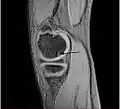

Magnetic resonance imaging (MRI) is useful for staging OCD lesions, evaluating the integrity of the joint surface, and distinguishing normal variants of bone formation from OCD by showing bone and cartilage edema in the area of the irregularity. MRI provides information regarding features of the articular cartilage and bone under the cartilage, including edema, fractures, fluid interfaces, articular surface integrity, and fragment displacement.[37][38] A low T1 and high T2 signal at the fragment interface is seen in active lesions. This indicates an unstable lesion or recent microfractures.[30] While MRI and arthroscopy have a close correlation, X-ray films tend to be less inductive of similar MRI results.[38]

Computed tomography (CT) scans and Technetium-99m bone scans are also sometimes used to monitor the progress of treatment. Unlike plain radiographs (X-rays), CT scans and MRI scans can show the exact location and extent of the lesion.[39] Technetium bone scans can detect regional blood flow and the amount of osseous uptake. Both of these seem to be closely correlated to the potential for healing in the fragment.[40][41]